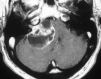

Histologic patterns of cellular architecture often suggest a tissue diagnosis. Distinctive histologic patterns seen within the peripheral nerve sheath tumor schwannoma include the Antoni A and Antoni B regions. The purpose of this report is to review the significance of Antoni regions in the context of schwannomas.